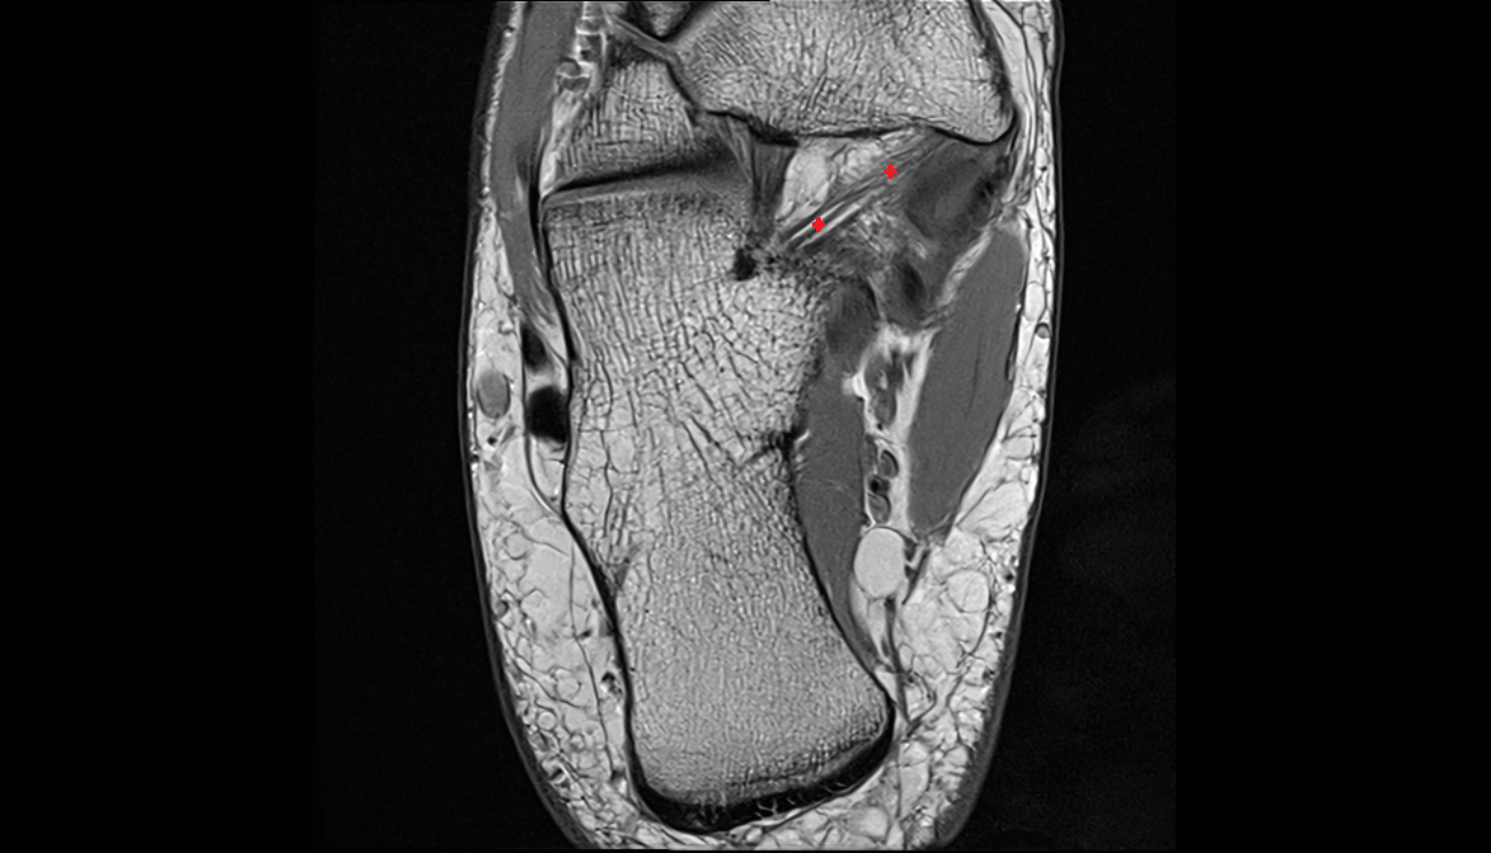

- Talus

- Calcaneus

- Ankle joint

- Talocalcaneal joint

- Talocalcaneonavicular joint

- Calcaneocuboid joint